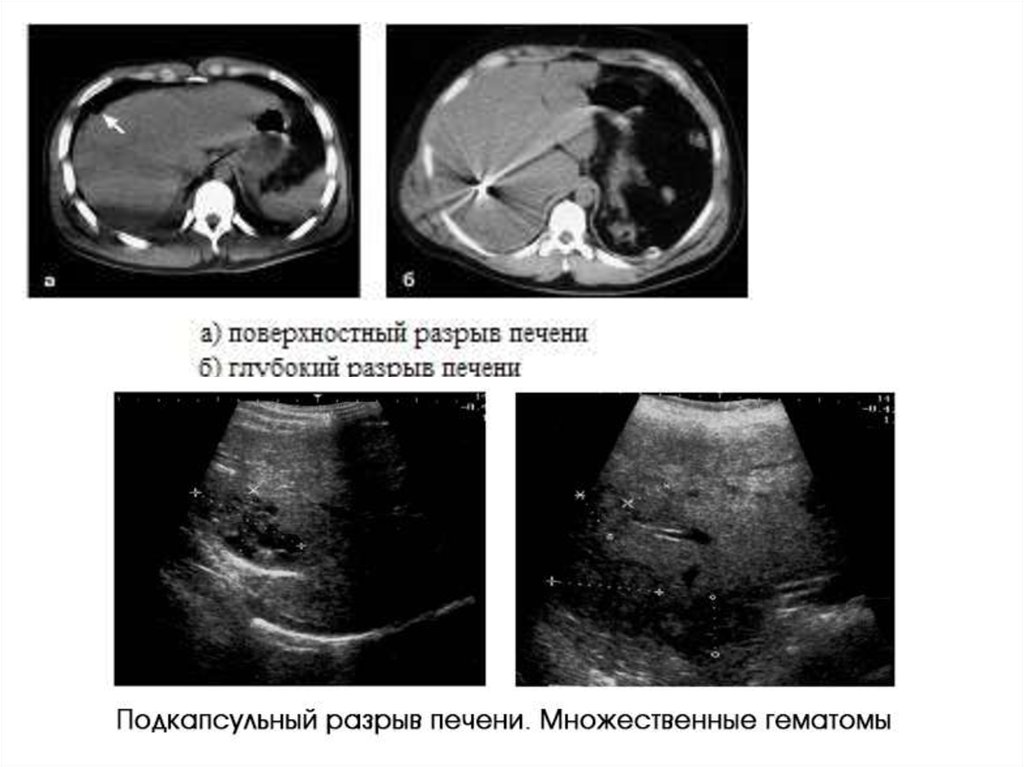

Повреждение органов брюшной полости